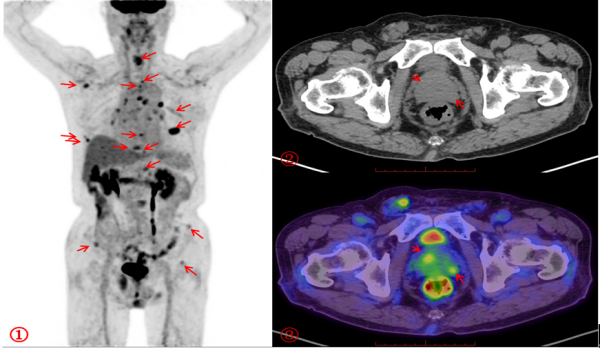

在医生的建议下,李昌乐接受了18F-FDG PET/CT检查(18F-FDG,全称氟代脱氧葡萄糖,是一种葡萄糖类似物)。通过这种“雷达式”扫描,医生发现老人前列腺外周带代谢轻度不均匀增高,延迟显像显示进一步增高,同时全身多发骨质异常,糖代谢异常增高,其余部位未见高代谢病灶。据此,医生立即锁定“元凶”为前列腺,考虑前列腺癌伴全身多发骨转移。

为进一步明确诊断和分期,医生又为李爷爷完善了PSA(全称前列腺特异性抗原,是前列腺癌肿瘤标志物)检测,并安排了18F-PSMA PET/CT检查(PSMA,全称前列腺特异性膜抗原,是一种与前列腺癌密切相关的蛋白质)。最终,PSMA PET/CT显像清晰显示出前列腺癌原发灶及转移灶的范围及大小,并且还发现了FDG PET/CT显像未能查出的微小骨转移灶及盆腔淋巴结转移灶。这一结果为临床医生提供了关键依据,避免了盲目手术或穿刺的风险,为治疗方案选择提供了有力支持。

FDG PET/CT显像① MIP图:箭头所示全身多处糖代谢异常增高灶为骨转移灶;③PET/CT融合图:箭头所示糖代谢异常增高处为前列腺癌原发灶(SUVmax约3.2),而②CT图显示密度无异常。